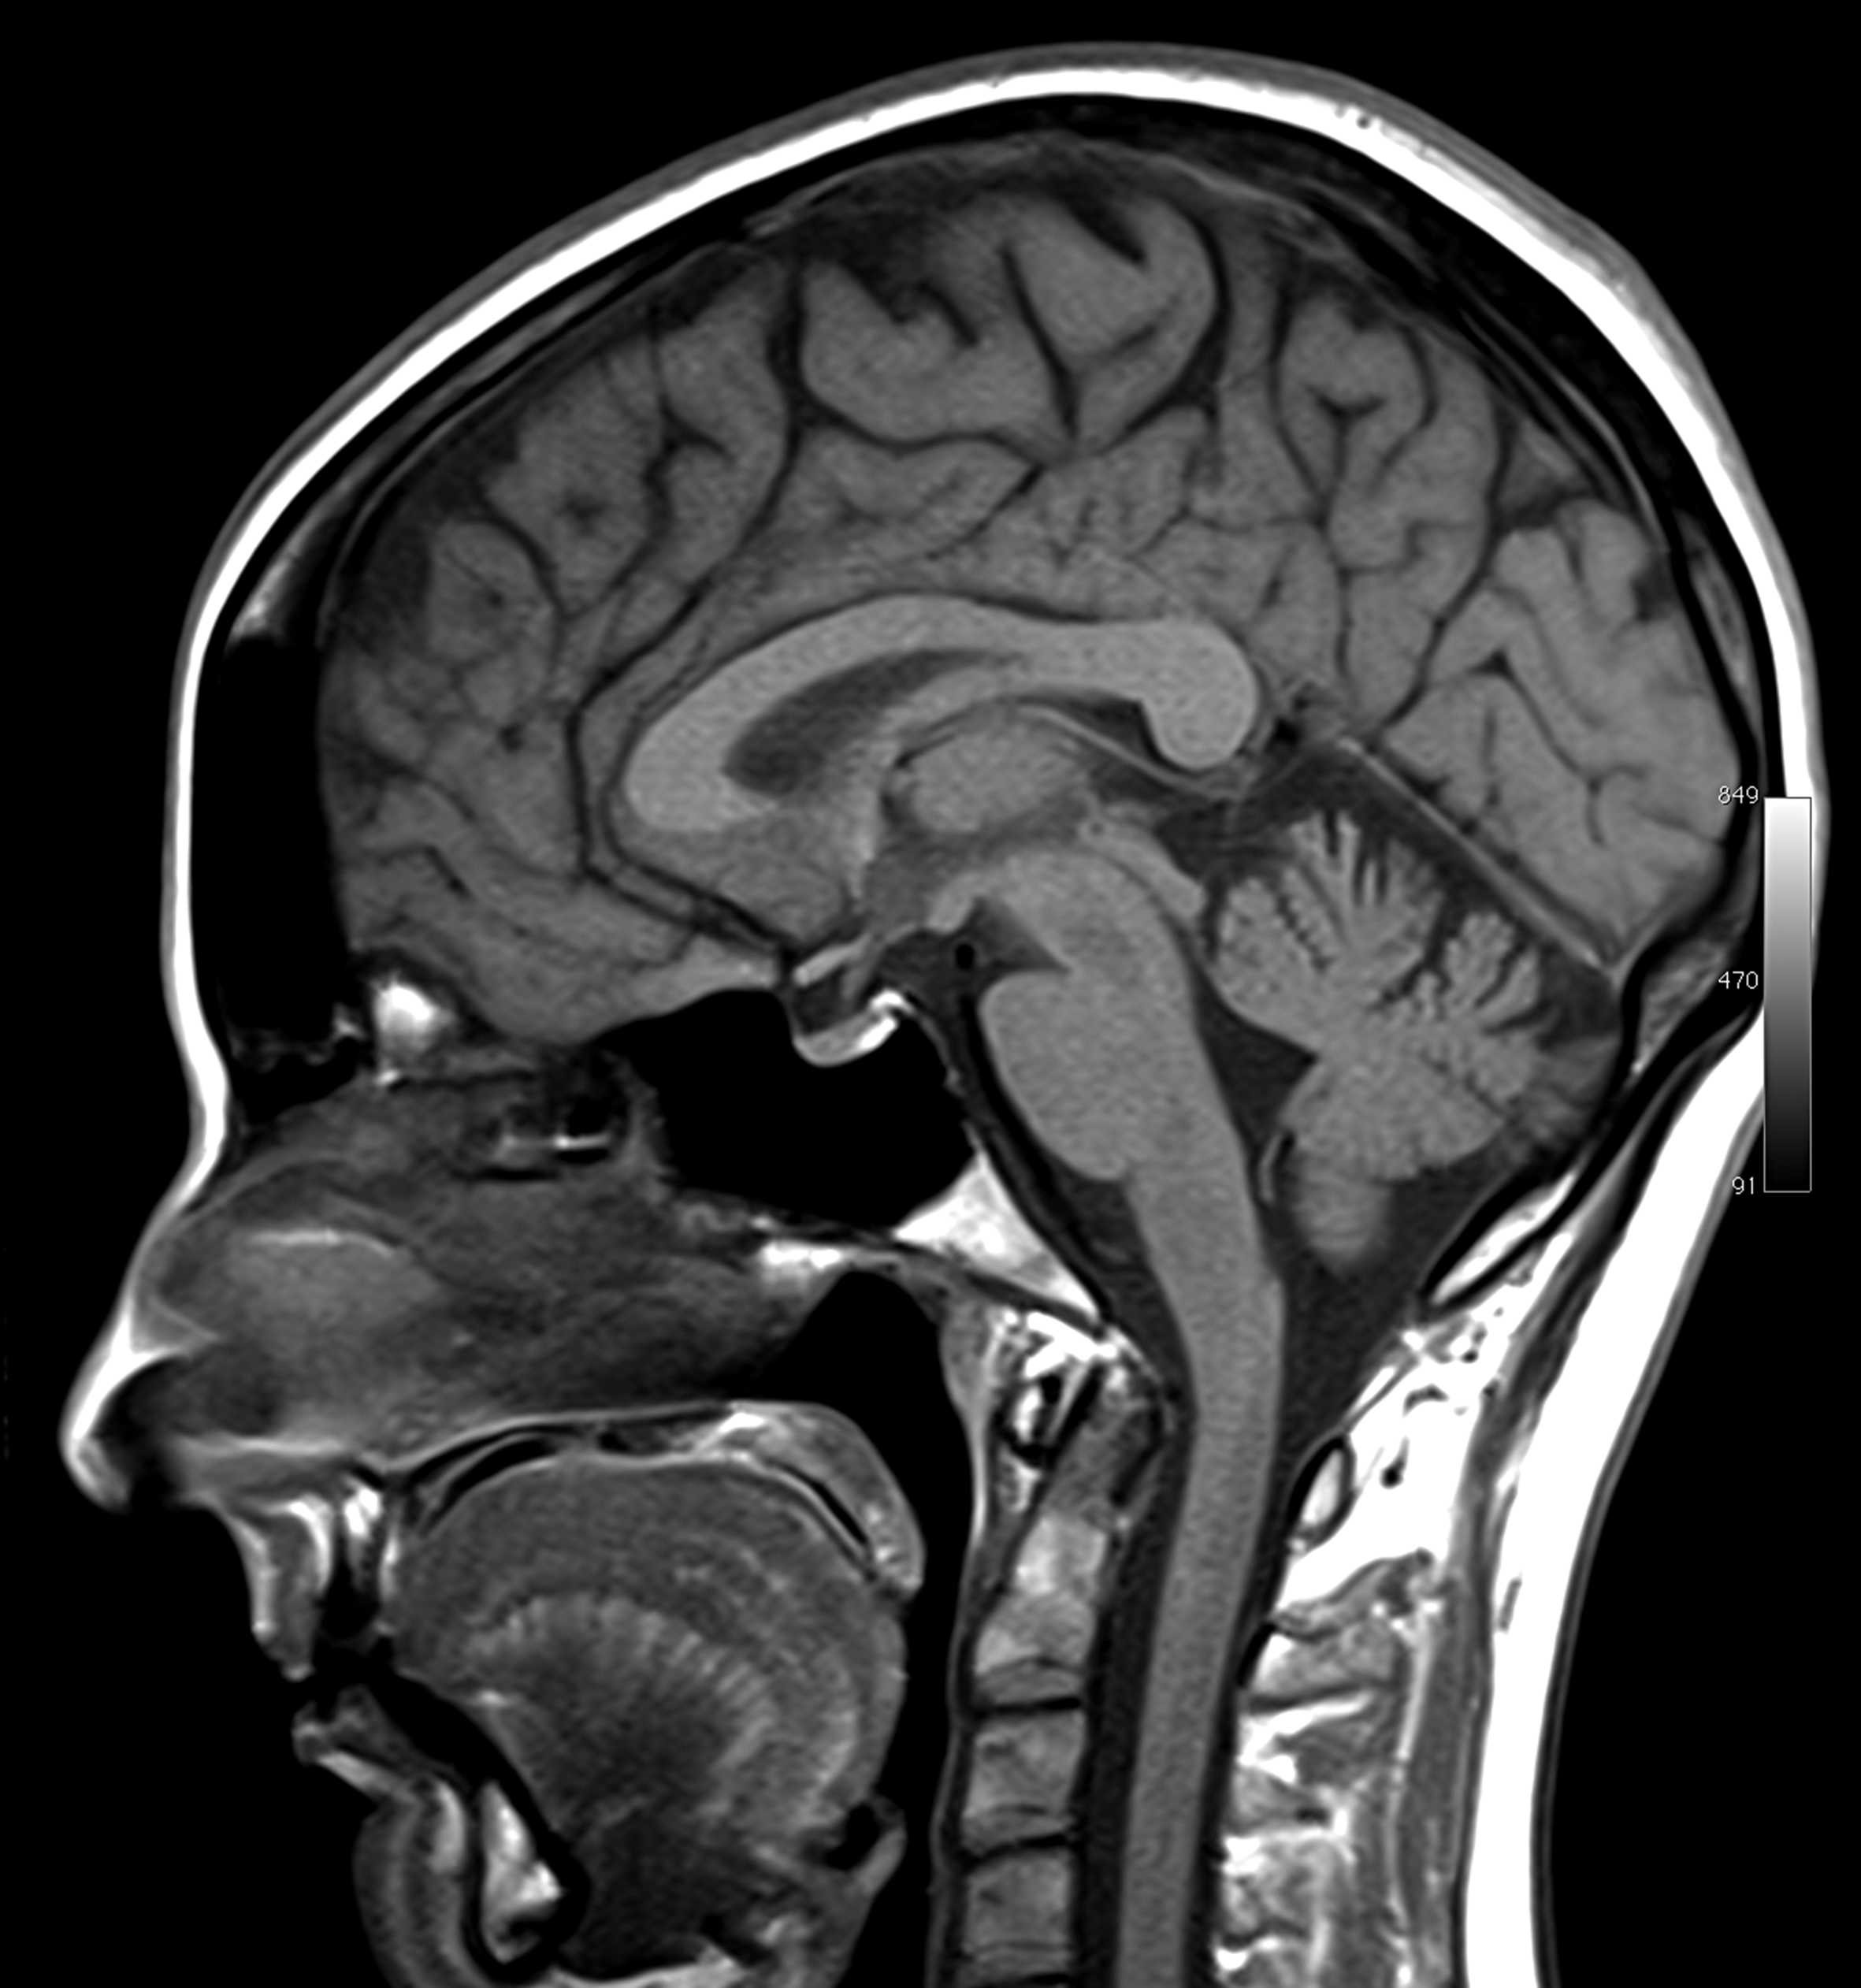

No estudo do corpo humano utilizam-se com frequência meios tecnológicos que permitem imagens do interior do nosso corpo, como a da figura seguinte obtida a partir de uma ressonância magnética.

Na imagem podem ver-se as cavidades...